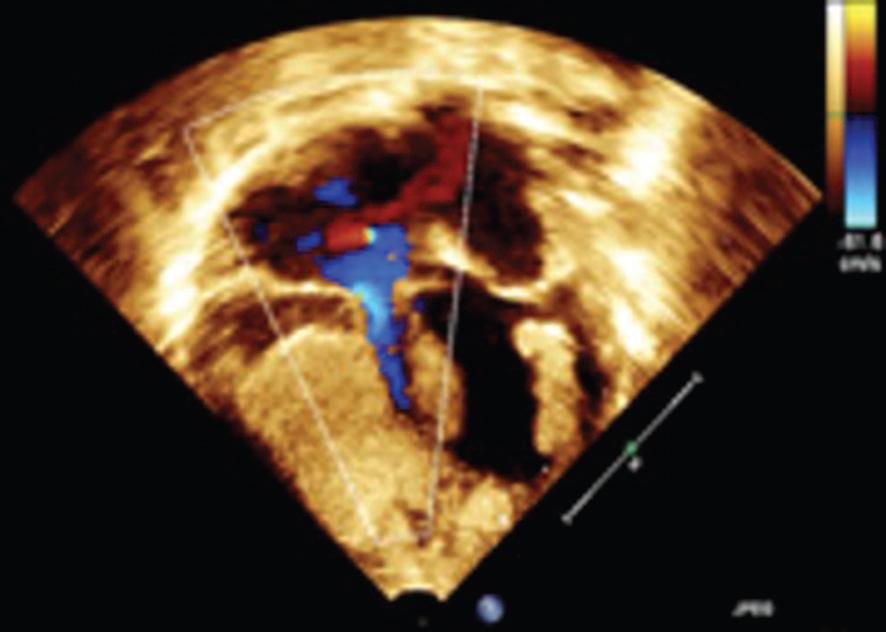

- El primer caso se trata de una paciente de 20 años de edad, sin antecedentes heredofamiliares de importancia, la cual inicia control de embarazo de alto riesgo en tercer nivel por múltiples amenazas de aborto. Derivada a nuestro hospital a las 36 semanas de gestación, realizándose el primer ecocardiograma prenatal por parte de nuestro servicio detectando tumores cardiacos compatibles con rabdomiomas, con imagen ecogénica en aurícula derecha de 18 mm y en ventrículo derecho de 20 mm con septum interventricular de 8 mm (Fig. 1), sin datos de obstrucción al tracto de salida, por lo que se decide continuar con el embarazo. Nace por cesárea, sin complicaciones. Se realiza ecocardiograma posnatal de control con los hallazgos previos, reportando tumoración a nivel de la cava superior de 13 x 18 mm, tumoración en surco atrioventricular de 15.4 x 4.5 mm, en ventrículo derecho con tumoración de 17.4 x 22 mm, siendo bilobulado, a nivel del ventrículo izquierdo con múltiples tumoraciones adheridas al septum y a la pared anterior la mayor de 7.7 x 8.2 mm (Fig. 2), corroboradas por resonancia magnética (Fig. 3). Debido a la asociación de tumores intracardiacos con esclerosis tuberosa fue valorado por el Servicio de Neurología, en donde mediante la realización de resonancia magnética de encéfalo se evidencia lesión nodular intraaxial en el giro recto derecho y nódulos subependimarios en ambos ventrículos laterales (Fig. 4), con hallazgos referidos que se encuentran dentro del espectro de esclerosis tuberosa. Se mantiene en vigilancia, en control por la consulta externa de dicho servicio.

Figura 2 Imagen del ecocardiograma posnatal del mismo paciente, donde se observa en cuatro cámaras 2D tumor en surco atrioventricular de 15.4 x 4.5 mm, en ventrículo derecho con tumor de 17.4 x 22 mm y a nivel del ventrículo izquierdo con múltiples tumores adheridos al septum y a la pared anterior la mayor de 7.7 x 8.2 mm.